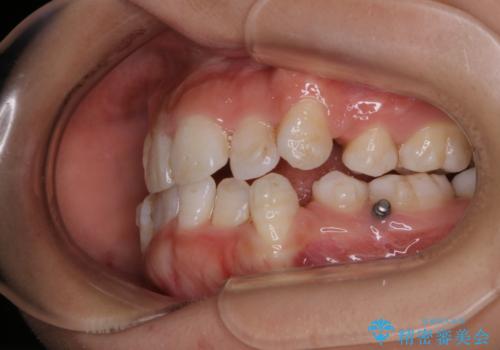

インビザライン単独での抜歯矯正治療

- 当院にてインビザライン治療を行っていた同僚の方からのご紹介でいらした方です。楽器を演奏されるとの事で、インビザラインによる矯正治療をご希望されました。治療の途中で一時的にワイヤー矯正に切り替える可能性もあることもご了承頂いた上で治療を行いました。

1日20時間以上、正しくインビザラインを使用して頂いたおかげで、ワイヤーに切り替えることなく矯正治療を終了することが出来ました。抜歯症例でしたが比較的短期間で見た目が劇的に改善し、大変喜んでいただけました。